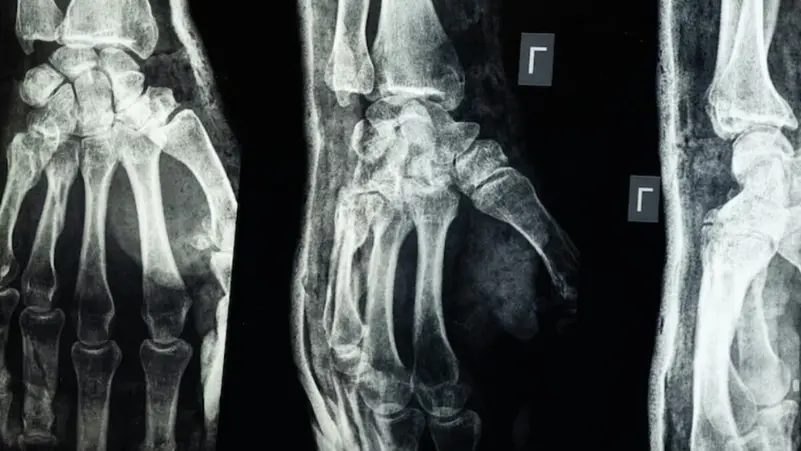

أعلن فريق بحثي في مقاطعة تشيجيانغ شرق الصين عن ابتكار طبي جديد يتمثل في “غراء عظمي” قادر على معالجة الكسور وتركيب الشظايا العظمية خلال ثلاث دقائق فقط، في خطوة وُصفت بأنها اختراق علمي في عالم جراحة العظام، بحسب ما نقل موقع “إن دي تي في” NDTV.

يحمل الابتكار الطبي الجديد اسم Bone-02، وقد استلهم رئيس الفريق الطبي الدكتور لين شيانفِـنغ، فكرته بعد ملاحظته للطريقة التي تلتصق بها المحار بجسور تحت الماء، بحسب ما نقلت عنه صحيفة “غلوبال تايمز”

وأوضح أن هذا الغراء يتميز بقدرته على التثبيت السريع والدقيق حتى في بيئة غنية بالدم، مع ميزة إضافية كونه يُمتَص طبيعياً من الجسم أثناء عملية الالتئام، ما يلغي الحاجة إلى عمليات جراحية لاحقة لإزالة المسامير أو الصفائح المعدنية.

وأكدت الاختبارات المعملية أن Bone-02 نجح في تحقيق نتائج جيدة من حيث السلامة والفعالية. وفي إحدى التجارب، أُجريت العملية في أقل من 180 ثانية (ثلاث دقائق)، بينما كانت طرق العلاج التقليدية تتطلب وقتاً وبحسب الاختبارات المعملية، تمكن الغراء من تحقيق قوة ربط تفوق 400 رطل، وقوة قص تبلغ نحو 0.5 ميغاباسكال، وقوة ضغط تقارب 10 ميغاباسكال. كما أظهرت التجارب على أكثر من 150 مريضاً نتائج ناجحة، ما يعزز احتمالية أن يصبح بديلاً للزراعات المعدنية التقليدية التي تُستخدم في تثبيت العظام. كما يقول العلماء إنه قد يقلل أيضًا من مخاطر العدوى.